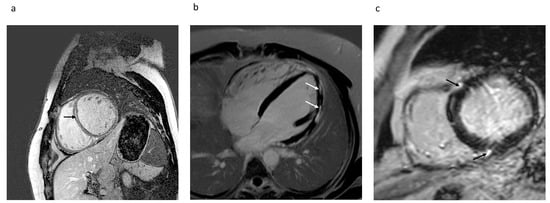

4.1.4. Location and Pattern of LGE and Association to VA

- Piers, S.R.; Tao, Q.; van Huls van Taxis, C.F.; Schalij, M.J.; van der Geest, R.J.; Zeppenfeld, K. Contrast-enhanced MRI-derived scar patterns and associated ventricular tachycardias in nonischemic cardiomyopathy: Implications for the ablation strategy. Circ. Arrhythm Electrophysiol. 2013, 6, 875–883. [Google Scholar] [CrossRef] [PubMed] [Green Version]